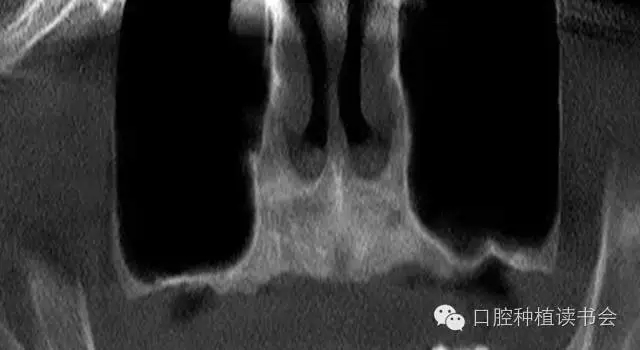

雖然牙槽脊垂直、水平吸收的程度幾乎相當(dāng),但是由于上頜后牙牙槽脊寬度較大,后牙區(qū)經(jīng)常出現(xiàn)圓鈍的、較寬的牙槽骨狀態(tài),臨床表現(xiàn)為剩余牙槽骨高度(Residual Bone Height,RBH)不足。在個別情況下,由于嚴(yán)重牙周病、根尖病等因素的影響,也會使牙槽脊水平寬度不足,表現(xiàn)為刃狀牙槽脊。上頜后牙一般為多根牙,當(dāng)牙周病和根尖病到一定程度后,磨牙才開始松動導(dǎo)致不能保留,又因上頜牙槽骨骨密度較低,在有些病例,牙槽脊重度吸收,RBH甚至不足1mm(圖1)。

▲(圖1)